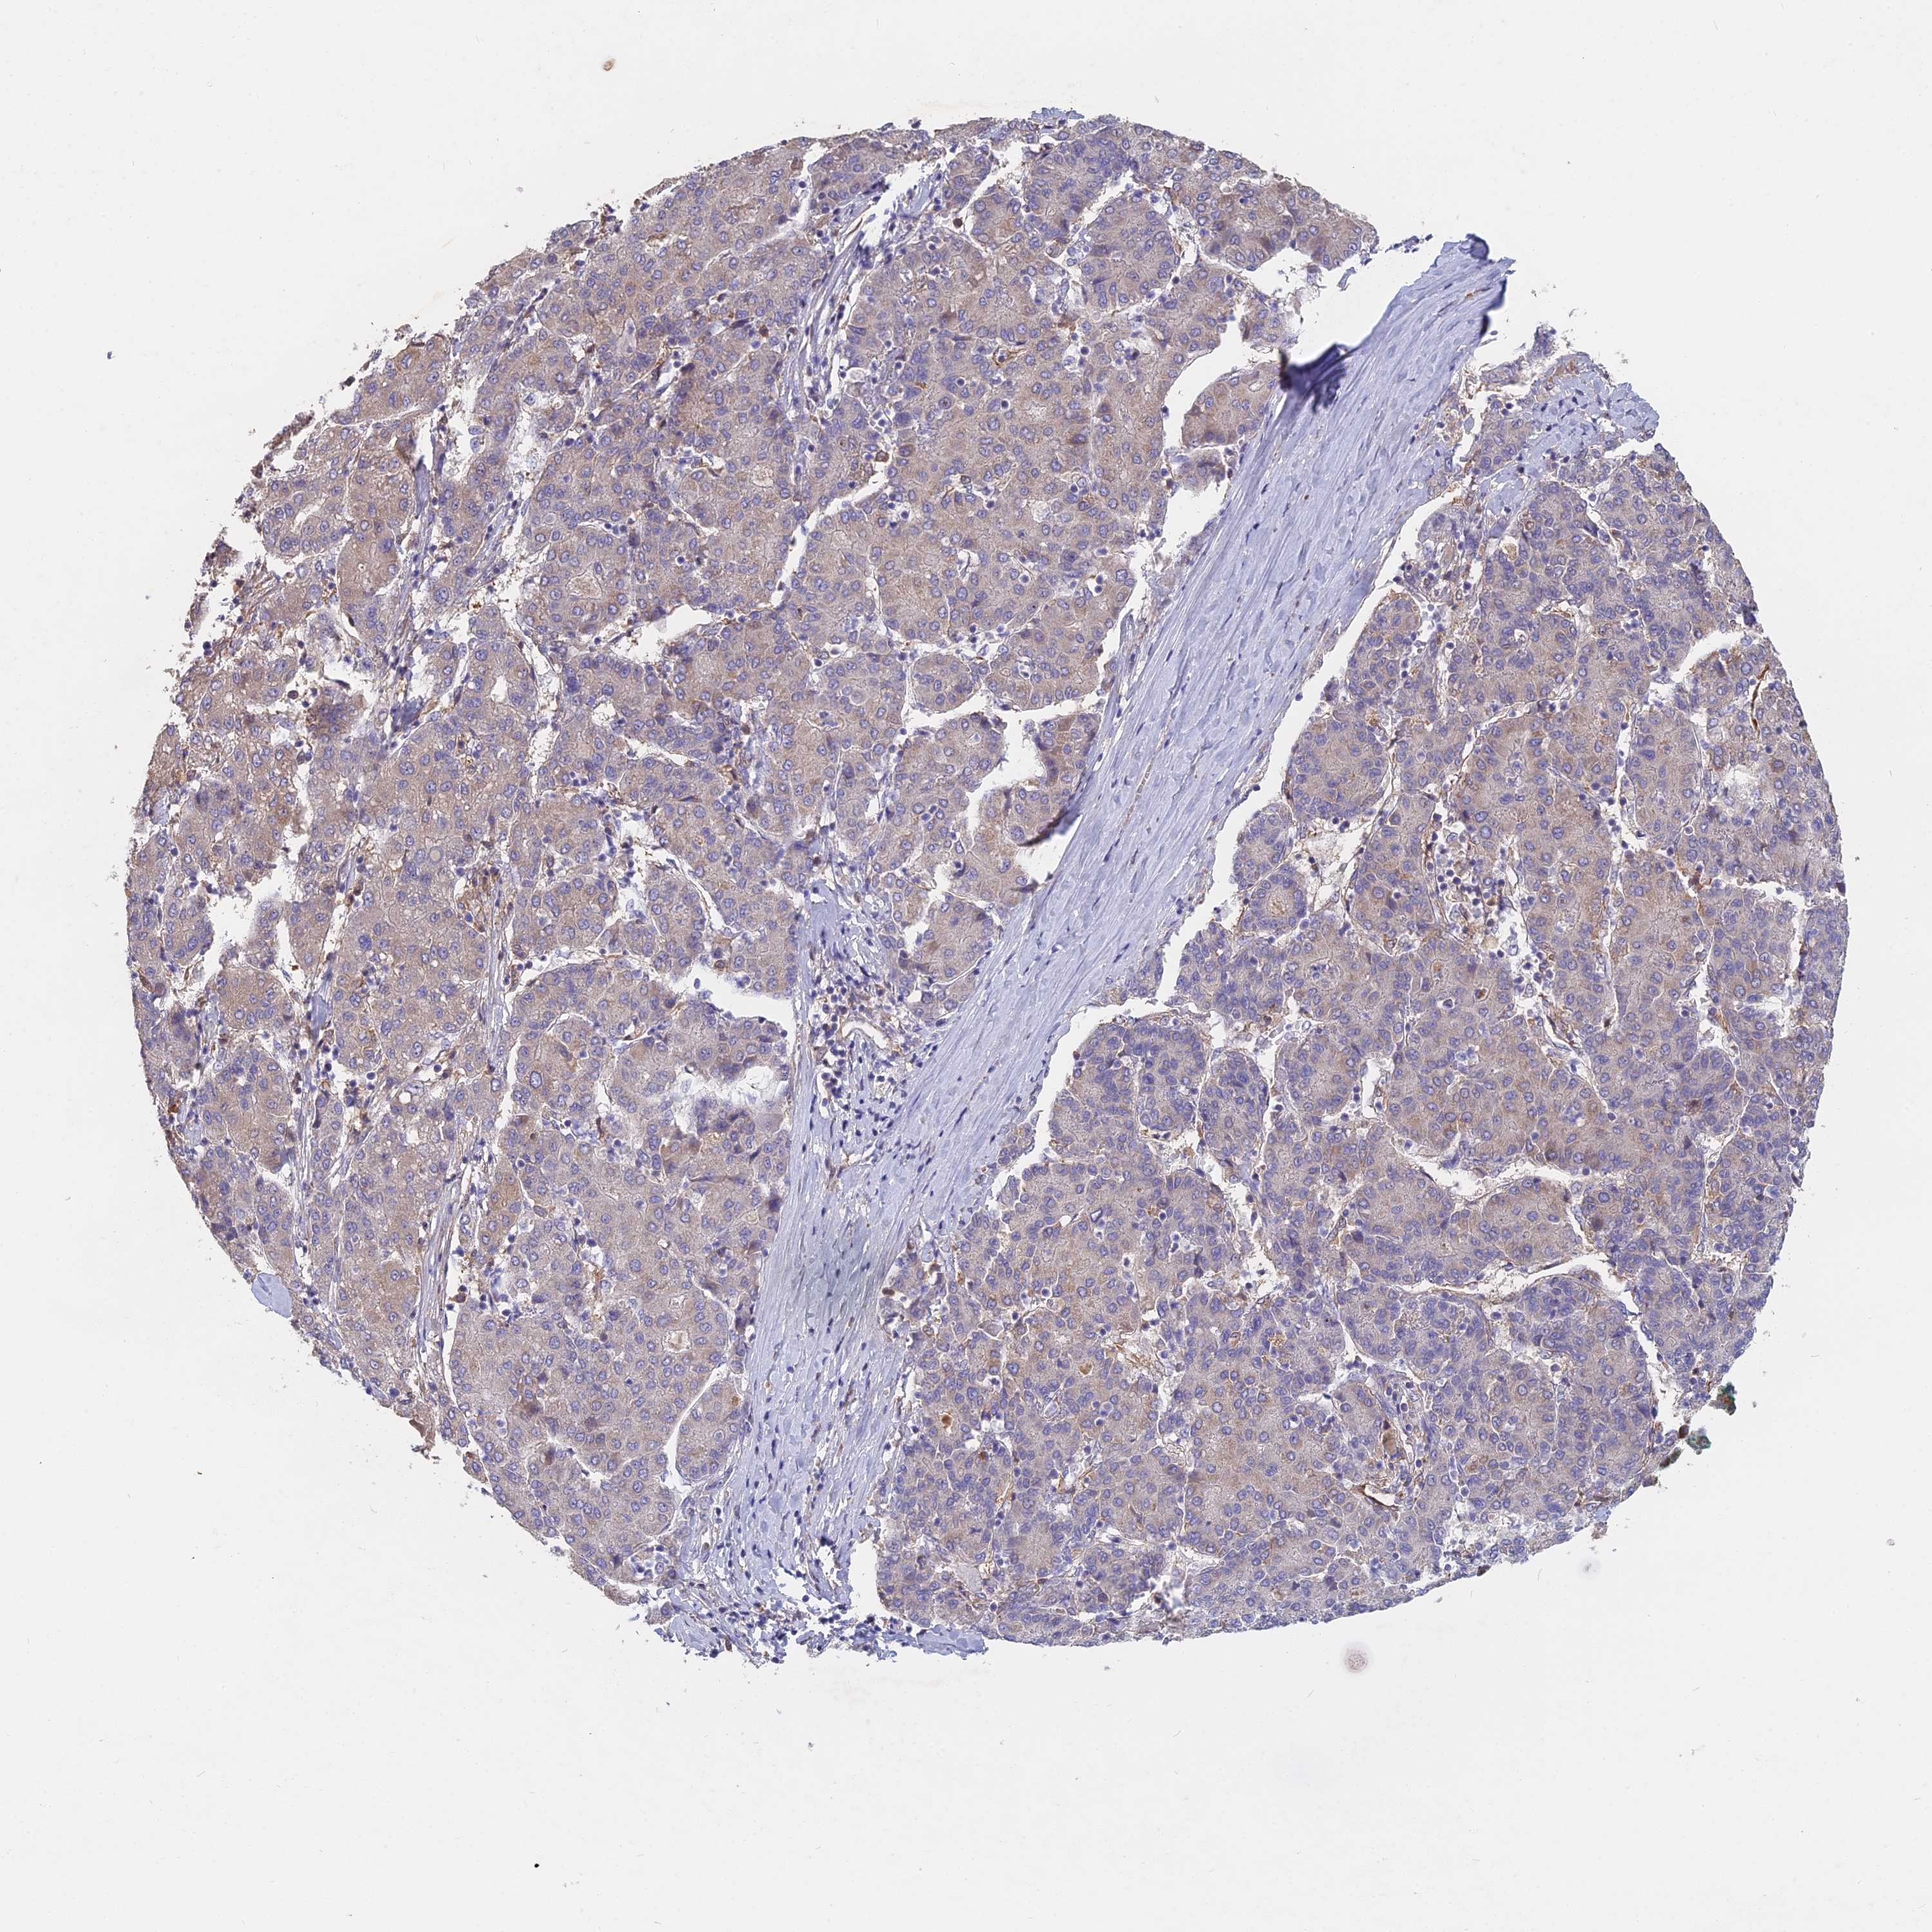

LIVER CANCER - Protein expressioni

A mouse-over function shows sample information and annotation data. Click on an image to view it in a full screen mode. Samples can be filtered based on level of antibody staining by selecting one or several of the following categories: high, medium, low and not detected. The assay and annotation is described here.

Note that samples used for immunohistochemistry by the Human Protein Atlas do not correspond to samples in the TCGA dataset.

Antibody stainingi

Antibody staining in the annotated cell types in the current human tissue is reported as not detected, low, medium, or high, based on conventional immunohistochemistry profiling in selected tissues. This score is based on the combination of the staining intensity and fraction of stained cells.

Each image is clickable and will lead to virtual microscopy that enables deeper exploration of all samples and also displays staining intensity scores, fraction scores and subcellular localization as well as patient and tissue information for each sample.

Antibody HPA042677

Staining

High

Medium

Low

Not detected

Intensity

Strong

Moderate

Weak

Negative

Quantity

>75%

75%-25%

<25%

None

Location

Nuclear

Cytoplasmic/membranous

Cytoplasmic/membranous,nuclear

Cholangiocarcinoma

Carcinoma, Hepatocellular, NOS